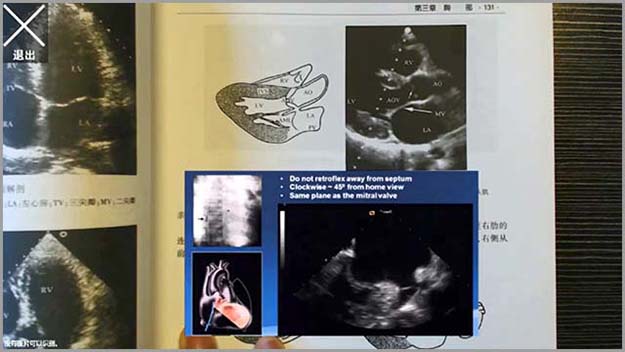

基礎醫(yī)學系列-增強現(xiàn)實醫(yī)學影(yΩ↑∏πǐng)像應用(yòng)解剖學

增強現(xiàn)實醫(yī)學影(yǐng)像應用(yòng)解剖學